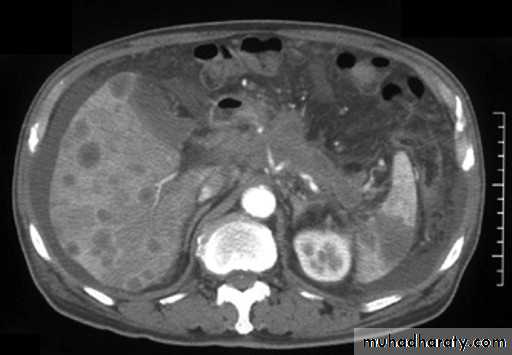

Malignant neoplasms:

hepatocellular carcinoma